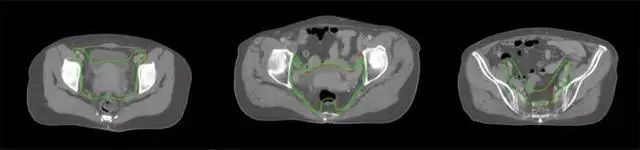

四、放射治療智能勾畫(huà)軟件

產(chǎn)品背景

放射治療,簡(jiǎn)稱(chēng)放療,是治療腫瘤主要手段之一,利用放射線破壞照射區(qū)(靶區(qū))的細(xì)胞,使腫瘤細(xì)胞停止分裂直至死亡,醫(yī)生通常把放射治療形象的比喻為“打靶”,放療前精準(zhǔn)勾畫(huà)腫瘤靶區(qū)范圍是腫瘤放射治療的關(guān)鍵步驟。傳統(tǒng)的靶區(qū)勾畫(huà)醫(yī)生會(huì)根據(jù)患者多張CT、MRI影像片憑借經(jīng)驗(yàn)進(jìn)行,比較耗時(shí),治療的病人數(shù)量也有限,且靶區(qū)勾畫(huà)缺少行業(yè)統(tǒng)一的規(guī)范和標(biāo)準(zhǔn),無(wú)法達(dá)到同質(zhì)化,勾畫(huà)精確度不理想。

技術(shù)原理

基于深度學(xué)習(xí)人工智能的放療靶區(qū)智能勾畫(huà)技術(shù)和自動(dòng)計(jì)劃技術(shù),基于全面的市場(chǎng)調(diào)研和臨床專(zhuān)業(yè)意見(jiàn),采用獨(dú)創(chuàng)的基于小樣本量的人工智能算法,實(shí)現(xiàn)放療靶區(qū)和危及器官的快速全自動(dòng)勾畫(huà)。

產(chǎn)品優(yōu)勢(shì)

縮短至幾分鐘內(nèi)便可完成,大幅提升了放療效率,且人工智能平臺(tái)完成的靶區(qū)勾畫(huà)可基本滿足臨床醫(yī)生需求,專(zhuān)家只需審核時(shí)細(xì)微調(diào)整,可顯著提高靶區(qū)勾畫(huà)的規(guī)范化及精準(zhǔn)度,讓放療智能化,標(biāo)準(zhǔn)化??筛采w食管癌、鼻咽癌、直腸癌、宮頸癌、肺癌等多種病種。